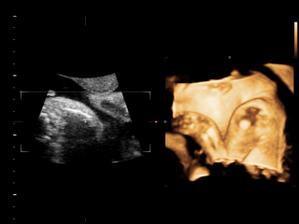

Náš pokladík v brušku

Naše chlapčiatko v 27tt+3...